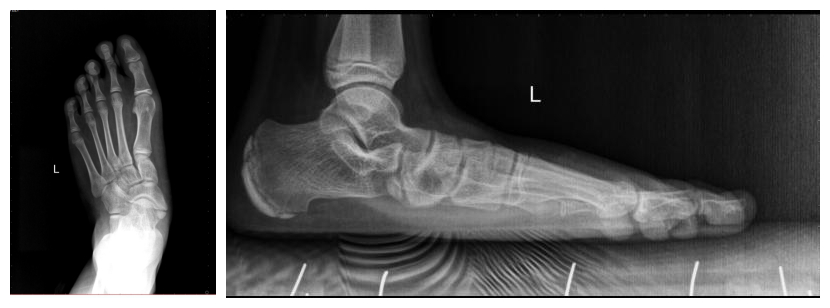

患者女,12岁,双足先天性平足症,患者自诉行走时双足疼痛7年余,就诊于多家医院均无法明确诊治。入院后,经我院医护团队细心查体及影像学分析,结合足踝外科最新的发展成果,为其制定了个性化的微创治疗方案。

过去治疗平足通常采用软组织和骨的重建手术方式,但此术式创伤大、疗效差、并发症多,使很多医生遇到这种病例非常棘手。如今,国外的临床研究证实,距下关节跗骨窦螺钉制动术在儿童及青少年可复性平足的治疗中取得了非常满意的效果,跗骨螺钉是一个特别的骨关节内部置入物,它是由医用钛合金制造,并且简单轻松的放入踝与脚后跟之间自然存在的空隙间,一次手术就可以恢复健康,且运动不受限制。